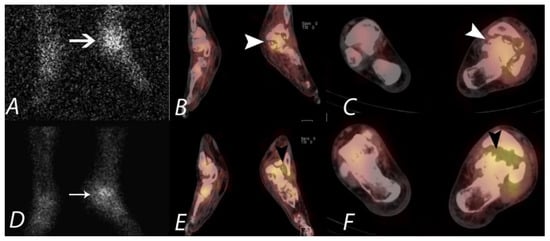

7. Knee Pain

- Mohan, H.K.; Gnanasegaran, G.; Vijayanathan, S.; Fogelman, I. SPECT/CT in imaging foot and ankle pathology-the demise of other coregistration techniques. Semin. Nucl. Med. 2011, 40, 41–51. [Google Scholar] [CrossRef]

- Leumann, A.; Valderrabano, V.; Plaass, C.; Rasch, H.; Studler, U.; Hintermann, B.; Pagenstert, G.I. A novel imaging method for osteochondral lesions of the talus—Comparison of SPECT/CT with MRI. Am. J. Sports Med. 2011, 39, 1095–1101. [Google Scholar]

- Wiewioski, M.; Rasch, H.; Jacob, A.L.; Valderrabano, V. Pain in osteochondral lesions. Foot Ankle Spec. 2011, 4, 92–99. [Google Scholar] [CrossRef]

- Breunung, N.; Fernando, R.; Gnanasegaran, G.; Vijayanathan, S.; Hosahalli, M.; Fogelman, I. Additional benefit of SPECT/CT in investigating heel pain. Clin. Nucl. Med. 2008, 33, 705–706. [Google Scholar] [CrossRef]